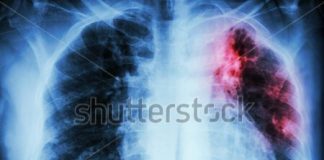

Tüberküloz veya Verem; Mycobacterium türlerinin neden olduğu, genellikle Mycobacterium tuberculosis'in neden olduğu uzun seyirli ve ...